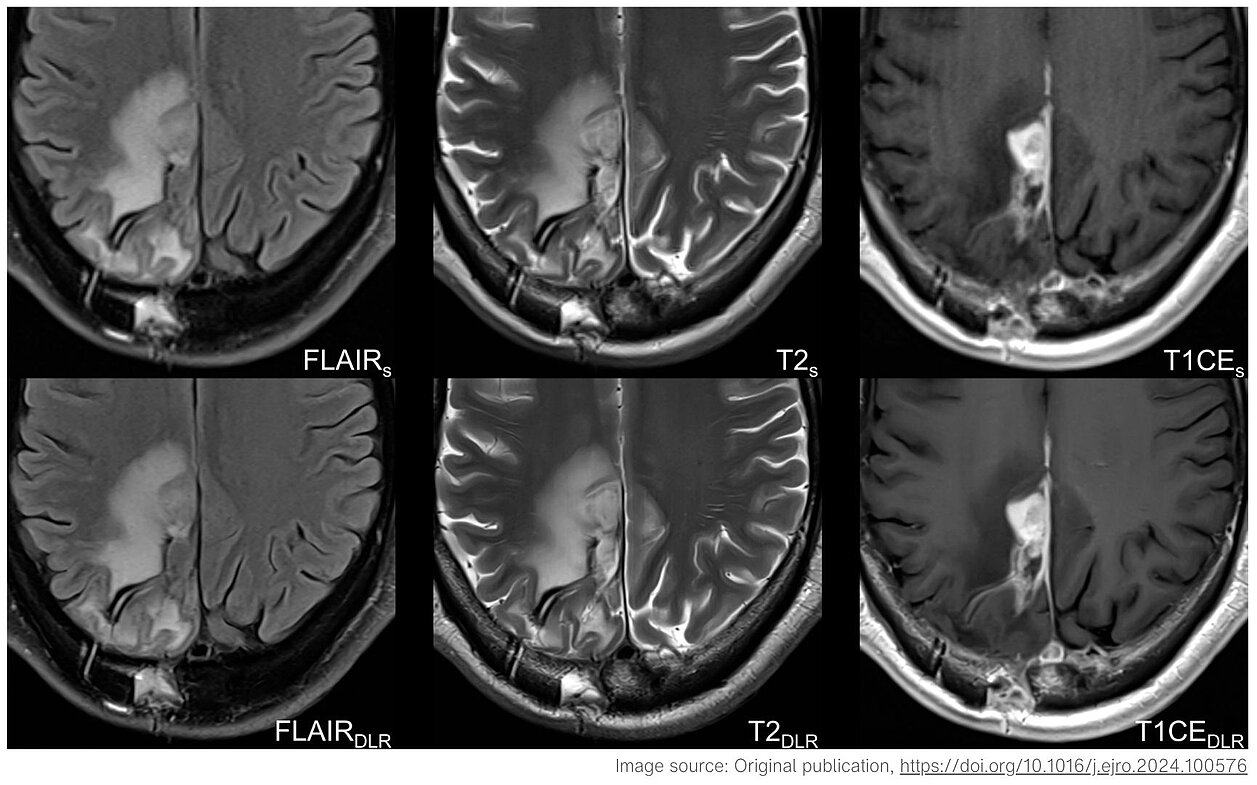

- Verbesserte Bildqualität: Die DL-optimierten MRT-Sequenzen zeigten eine überlegene Bildqualität, einschließlich schärferer Bilder, besserer Tumorsichtbarkeit und reduziertem Rauschen, was die diagnostischen Möglichkeiten insgesamt verbesserte. Diese Verbesserungen sind entscheidend zur Bewahrung einer hohen Diagnosesicherheit und -genauigkeit.